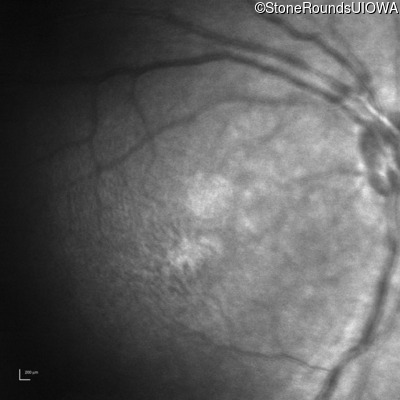

Infrared Fundus Photograph - Left - 10/40

Exemplar